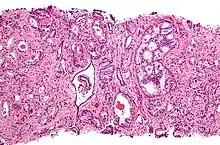

Gleason pattern 4. H&E stain.

• Pattern 4 - The tissue has few recognizable glands. Many cells are invading the surrounding tissue in neoplastic clumps. This corresponds to a poorly differentiated carcinoma.

Gleason pattern 4 glands are no longer single/separated glands like those seen in patterns 1-3. They look fused together, difficult to distinguish, with rare lumen formation vs Gleason 1-3 which usually all have open lumens (spaces) within the glands, or can be cribriform-(resembling the cribriform plate/similar to a sieve: an item with many perforations). Fused glands are chains, nests, or groups of glands that are no longer entirely separated by stroma-(connective tissue that normally separates individual glands in this case). Fused glands contain occasional stroma giving the appearance of "partial" separation of the glands. Due to this partial separation, fused glands sometimes have a scalloped (think looking at a slice of bread with bite taken out of it) appearance at their edges.[4][7]